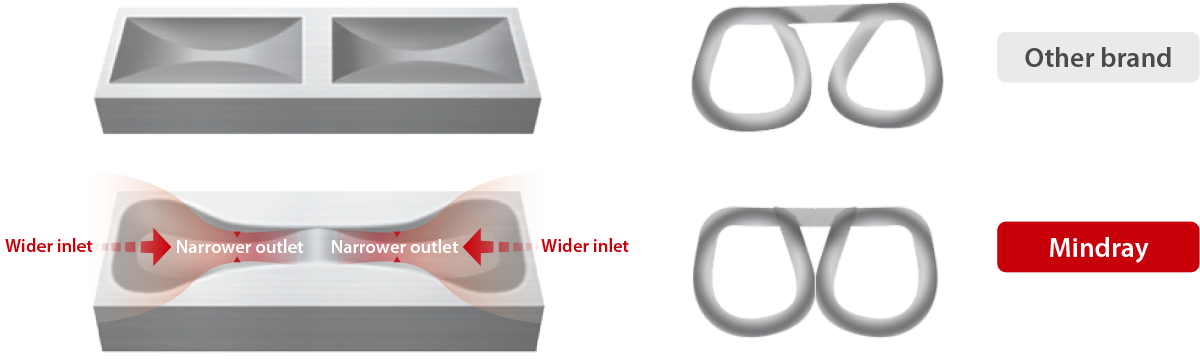

Better Staple Formation

Enhances Staple Line Security

Dumbbell-shaped staple pocket

The inlet is 35% wider, reducing the possibility of staple legs tip disengaging from the pocket;

The outlet is 60% narrower, enabling more uniform and consistent staple formation.